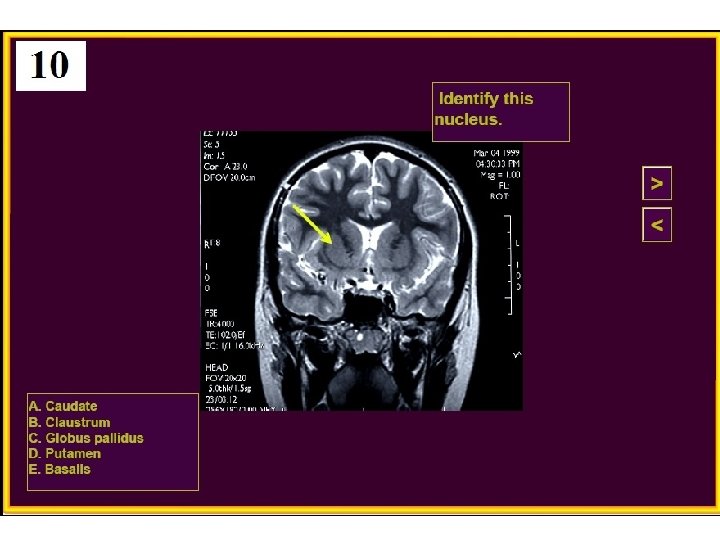

20. Huntington’s disease is caused by degeneration of which nucleus? A) Subthalamic B) Globus pallidus C) Substantia nigra D) Caudate E) VPL